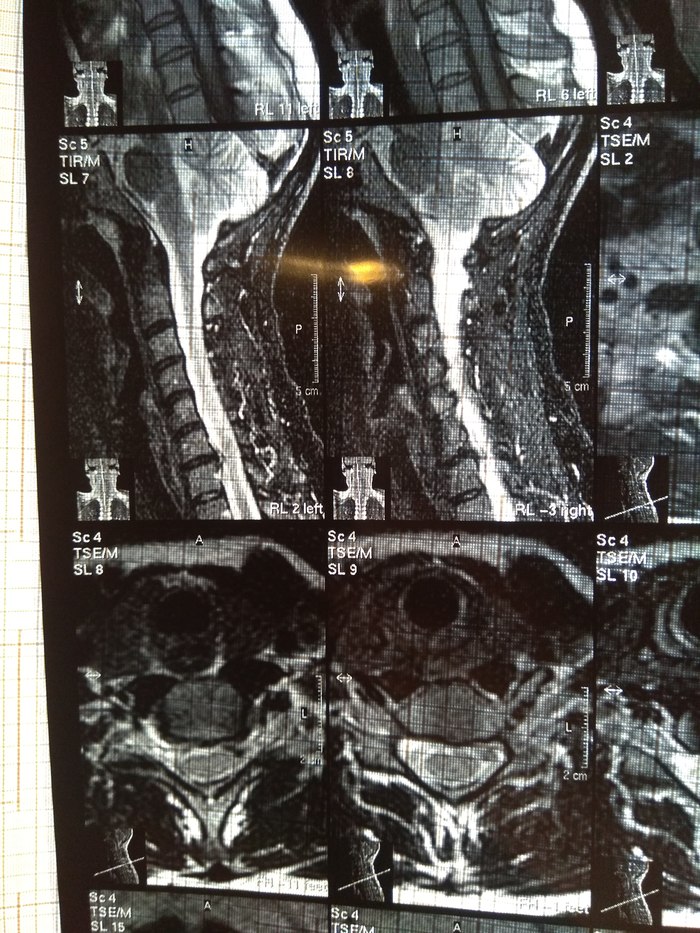

У подруги случилась проблема, тянула с визитом к врачу и в итоге потеряла сознание, вызывали скорую и направили к неврологу. Онемение пальцев на правой руке, сильные боли до судорог и потери сознания. В итоге невролог направил на МРТ и к нейрохирургу, выписали ношение ортопедического воротника, 2 вида уколов и таблетки, названия навскидку не помню. Сказали если через 10 дней не полегчает, то на операцию. Сегодня 5й день, никаких улучшений, рука с каждым днем выше немеет, но подвижность пока в норме. В день по 2-3 раза колет кетонал. Я вот переживаю как бы рука не отказала. Такое может случиться?